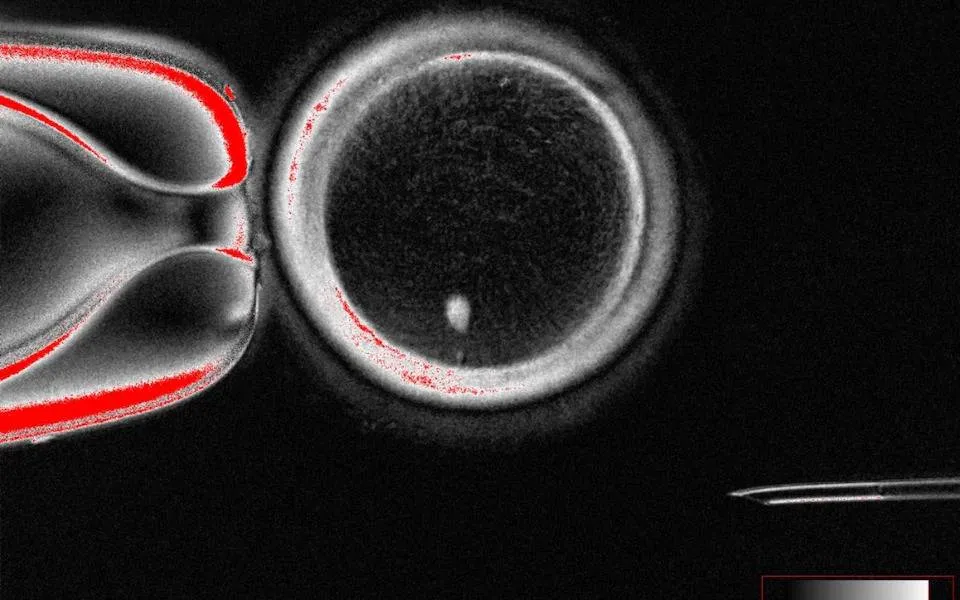

وعندما خصّب الفريق البويضة بالحيوان المنوي، بدأت النمو لتتحول إلى جنين، حتى توقفت التجربة عند اليوم السادس، وهو الموعد الذي يُنقل فيه الجنين إلى الرحم عن طريق التلقيح الصناعي.

وتُسمى هذه العملية الجديدة «انقسام الخلية»، وتبدأ بعملية الاستنساخ نفسها -نقل النواة من خلية جلدية إلى بويضة متبرعة- ثم تُجبر البويضة على التخلي عن 23 من كروموسوماتها.

وتُنتج هذه التقنية بويضة قابلة للحياة، قادرة على الاندماج مع الكروموسومات الـ23 من الحيوان المنوي، محاكيةً عملية الإخصاب الطبيعية، ويمكن بعد ذلك زرع الجنين الناتج في رحم الأم أو رحم بديل.

ونجح الفريق في إنتاج 82 بويضة وظيفية، جرى تخصيبها في المختبر، على الرغم من أن 9 في المائة فقط منها تطورت إلى أجنة مبكرة، تعرف باسم الكيسة الأريمية، وعانت جميعها تشوهات كروموسومية.